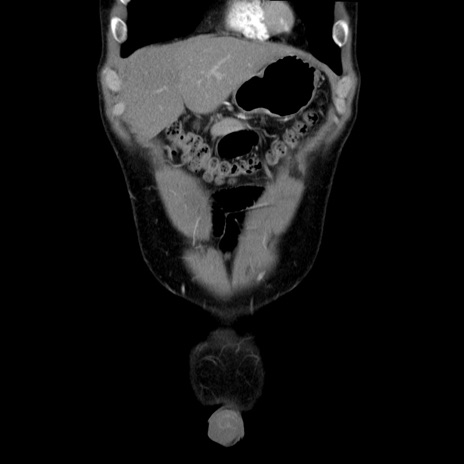

症例36(冠状断像)

【症例】20歳代 男性

【主訴】心窩部痛

【現病歴】今朝より上腹部痛あり。一旦軽快していたが再度出現したため救急要請。昨日夕に白身の魚を含む刺身を食べた。

【身体所見】BP 136/89mmHg、HR 74/min、BT 37.0℃、腹部:膨満、軟、心窩部に圧痛あり。反跳痛なし、筋性防御なし、腸雑音やや亢進あり。

【データ】WBC 17700、CRP 0.48